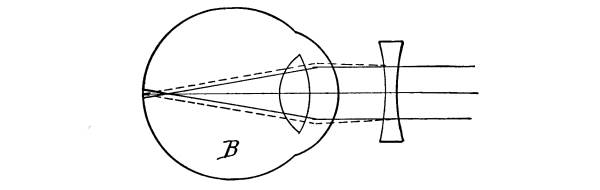

The Nose, 57—The Sense of Smell, 58—The Mouth, 59—The Hyoid Bone, 60—The Teeth, 60—The Sense of Taste, 61—Salivary Glands, 61—The Tonsils, 62—The Ear, 63—Eustachian Tubes, 63—Sensation of Hearing, 65—The Eye, 66—Lachrymal Gland, 68—Coats of the Eye, 68—Light Rays and Sight, 70—Accommodation, 72—Color Perception, 73. |